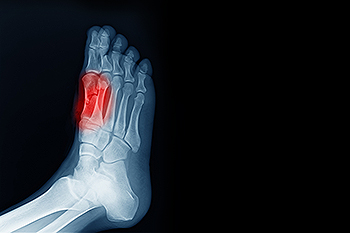

In many cases the cause of toe pain is obvious, but in others, a podiatrist may want to use more advanced methods to determine the problem. These can range from simple visual inspections and sensation tests to X-rays and MRI scans. Prior medical history, family medical history, and any recent physical traumatic events will all be taken into consideration for a proper diagnosis.

Treatments for toe pain and injuries vary and may include shoe inserts, padding, taping, medicines, injections, and in some cases, surgery. If you believe that you have broken a toe, please see a podiatrist as soon as possible.

Toe pain can originate from corns, calluses, hammertoes, and bunions, as well as ingrown toenails, sprains, fractures, and dislocations. Corns develop as the toe rubs against the inside of a shoe which causes the skin to thicken as a form of protection. A corn is typically cone-shaped and has a small, hardened spot that points inward. When a corn is pressed into the skin, the toe becomes painful. Corns usually form on the top or side of the toe. A callus is also a thickened patch of skin that generally forms on the bottom of the foot. Calluses are the result of friction from the toe rubbing against the inside of a shoe. They may also occur by walking barefoot or having flat feet. A hammertoe is a bump on the knuckle of the second toe that is produced by wearing shoes that are too short for your feet. The bony protrusion rubs against the top of the shoe causing pain and irritation. A bunion is a malformation of the big toe. The base of the big toe pushes away from the smaller toes, forcing the top of the big toe to press toward the other toes. Bunions can be hereditary, or they can result from injury to the toe joint or from wearing high heels with a narrow toe box. The toe becomes inflamed, and a bump may develop at the end of the misplaced bone. Ingrown toenails typically affect the big toe and its surrounding skin. The nail will dig into the skin and become painful. Wearing tight or narrow shoes that compress the big toe causes the nail to grow into the fleshy part of the toe. Cutting toenails incorrectly can also add to the development of an ingrown toenail. A toe sprain originates from a torn or stretched ligament. Strapping the injured toe to the toe next to it for stabilization is common. A broken or fractured toe usually occurs from trauma like dropping a heavy object on it or bumping into something extremely hard and rigid. Osteoporosis, a thinning of the bones, can also bring about toe fractures.